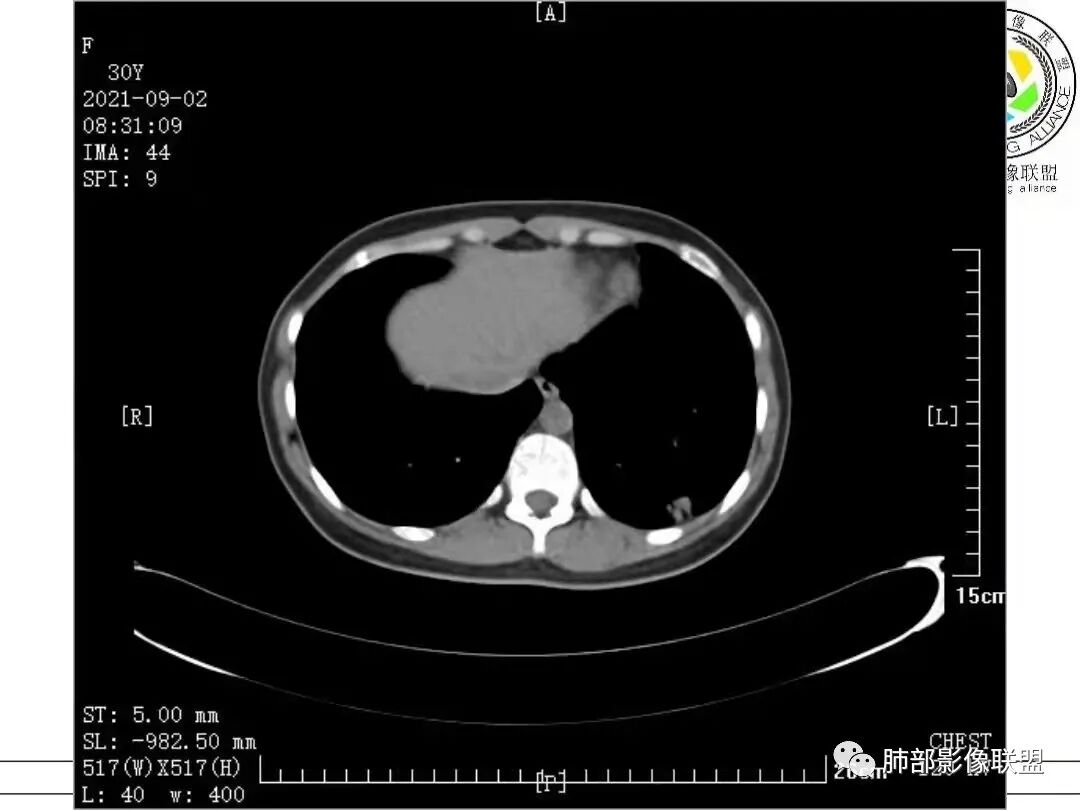

病例一

1.病例一:68岁男性,体检发现肺结节,肿瘤标志物CA199、CA50、CEA升高,其中CEA升高显著,超过正常范围的5倍以上。右肺下叶胸膜下结节影,整体较膨隆,部分层面可见锯齿状边缘,边界清晰,周围可见细毛细影,可见血管集束征、胸膜牵拉。密度不均,可见磨玻璃密度区及空泡征,胸膜下脂肪间隙显示不清。增强后显示轻、中度强化。

中老年男性,右肺下叶结节,增强边缘强化,首先考虑肺腺癌,鉴别肺隐球菌。

老年男性,cea,ca199显著升高。右肺下叶胸膜下结节,膨隆、小分叶、空泡征,边界清楚,细毛刺,支气管进入后鼠尾状狭窄,血管集束,不均匀中度强化,考虑肺腺癌,鉴别隐球菌。

右肺下叶胸膜下实性结节,边界清晰,边缘稍有膨胧,血管进入,内部可见空泡征,薄层示支气管截断,强化不均匀,CEA高,支持腺癌。